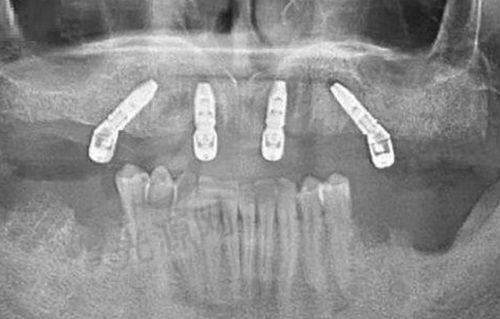

广州尚美口腔诊所是一家综合性口腔医院,集口腔种植、口腔矫正、口腔美容、口腔修复、儿童口腔、口腔综合治疗等多项目于一体。无论是牙齿缺失需要种植修复,还是牙齿不整齐想要矫正,亦或是进行口腔美容、修复等,在这里都能找到对应的诊疗服务。

比如口腔种植项目,能帮助那些牙齿缺失的患者重新拥有健康的牙齿;口腔矫正则可以改善牙齿排列不齐的问题,让患者拥有整齐美观的牙齿;口腔美容可以提升牙齿的美观度,让笑容更加自信;口腔修复能解决牙齿损坏等问题;儿童口腔专门针对儿童的口腔特点进行诊疗和保健;口腔综合治疗则涵盖了常见的口腔疾病治疗等。